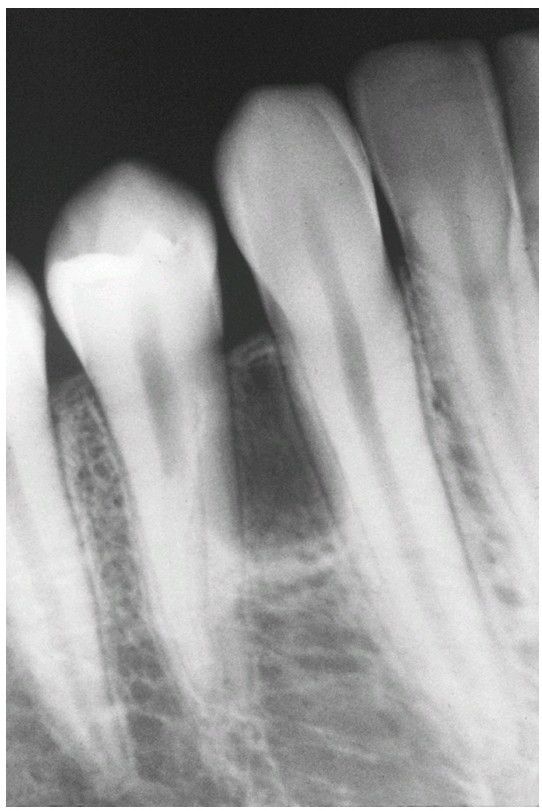

Lateral Periodontal Cyst.

Radiolucent lesion between the roots of a vital mandibular canine and first premolar.